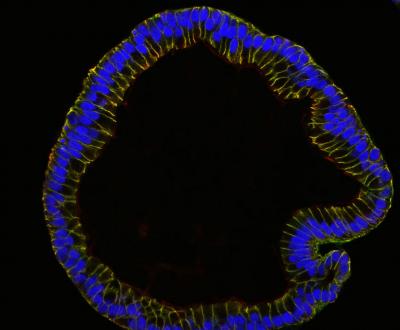

Until now, research into the origins and etiology of the diseases has also been restricted because fallopian epithelial cells cannot readily be grown in the laboratory. Together with researchers at the gynecology centers of the Charitè University Hospital, a team led by Thomas F. Meyer at the Max Planck Institute for Infection Biology in Berlin has now harnessed a new method of growing human epithelial cells as hollow spheres, so called 'organoids', in order to culture cells from clinical fallopian tube samples. By adapting the culture conditions to the specific needs of the tissue, they were able to keep the adult stem cells of the fallopian tube alive, so that they continue to proliferate and produce the cells typical of this tissue.

Importantly, the fallopian organoids have the same composition and structure as the epithelial lining of the tube. 'We have learned not only how to achieve conditions that allow cells to develop all features present in the human body, but also how to control their specialization into the different cell types found in the fallopian tubes' says Mirjana Kessler, the first author of a paper that just appeared in Nature Communications . 'The fallopian tube represents a crucial organ for female health: it is accessible to pathogenic microbes such as Chlamydia and at the same time provides a conduit into the abdominal cavity. It is the site of origin of several clinically important diseases for women, such as ovarian cancer, pelvic inflammatory disease and infertility.'